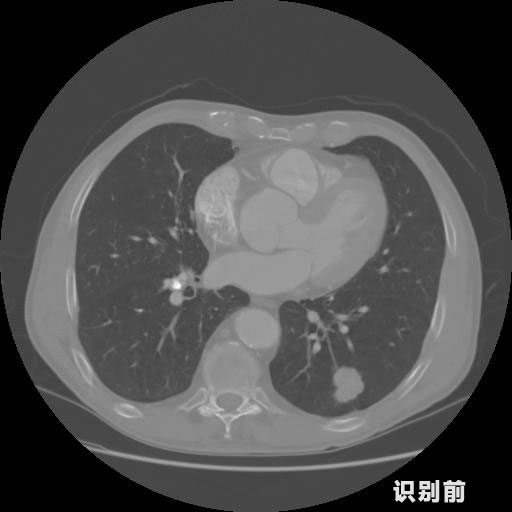

英特健康AI深度学习医疗图像识别系统案例_胸部CT

03.jpg